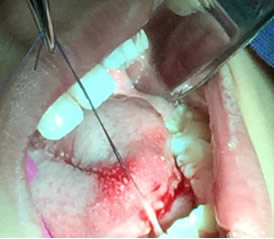

• Se colocó anestesia tópica y se infiltró localmente (lidocaína con epinefrina de 1: 100 000 al 2 %) a cada lado del frenillo lingual bloqueando nervio lingual bilateralmente. (Figuras 1 y 2).

Figura 1. Anestesia Local a cada lado del frenillo.

Figura 2. Anestesia Local del nervio lingual bilateralmente